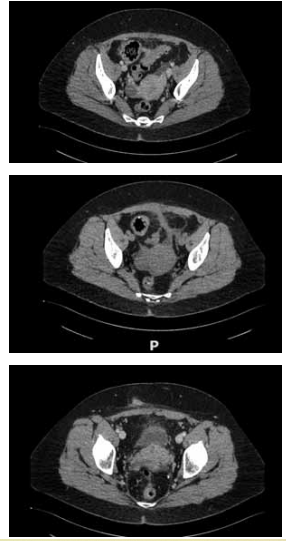

Mulher de 65 anos, com necessidade de toracocentese

de alívio por extenso derrame pleural à esquerda, que

causava dispneia. Realizada punção no 8o

espaço intercostal, linha axilar média, com saída de 20 mL de líquido serossanguinolento, sem saída adicional de líquidos.

Trinta minutos após o procedimento, a paciente evolui

descorada, com frequência cardíaca de 100 bpm e PA

de 85 x 60 mmHg, queixando-se de dispneia e dor abdominal. Realizou a tomografia demonstrada nas imagens

a seguir:

No retorno da tomografia, a paciente evolui com queda do nível de consciência, sendo realizada intubação orotraqueal. Assim, qual conduta mais adequada para resolução do caso?